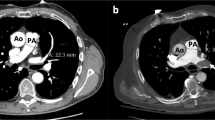

Multidetector computed tomography

Assessment of CT

Except for an increased PASP (40 ± 12 mmHg), mean values for echocardiographic RV variables were within normal range (Table 1). Tricuspid regurgitation was present and measurement of gradient feasible in 56 (66 %) patients. Tricuspid regurgitation was mostly mild (45 patients). Comparison of severity of CT clot burden with echocardiographic variables showed an inverse correlation for FAC (r = −0.57, Fig. 1), and a direct correlation for PASP (r = 0.51). A poor correlation was observed for MPI (r = 0.32) and CT scores, and no significant correlation was found for tissue Doppler s’ velocities.